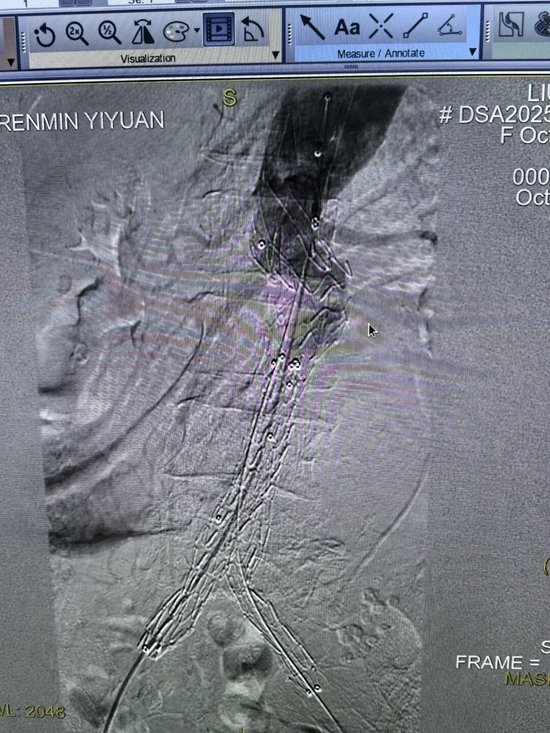

经过专家团队的全面评估和审慎决策,认为唯有行腹主动脉瘤腔内修复术(EVAR),才有一线生机。这是一种微创介入手术,仅需在双侧大腿根部切开约2厘米的小切口,通过股动脉将覆膜支架系统精准输送到动脉瘤部位,像搭桥一样在血管内建立起一道坚固的“屏障”,隔绝破裂的瘤腔,从而达到止血和治愈的目的。

尽管手术方案最优,但患者高龄、血管条件差、耐受能力低,术中任何一个环节出现闪失都可能导致失败。医护团队凭借精湛的技术和丰富的经验,成功将覆膜支架精准释放到位。

造影显示,支架定位完美,动脉瘤被完全隔绝,活动性出血瞬间停止,手术取得了决定性成功!